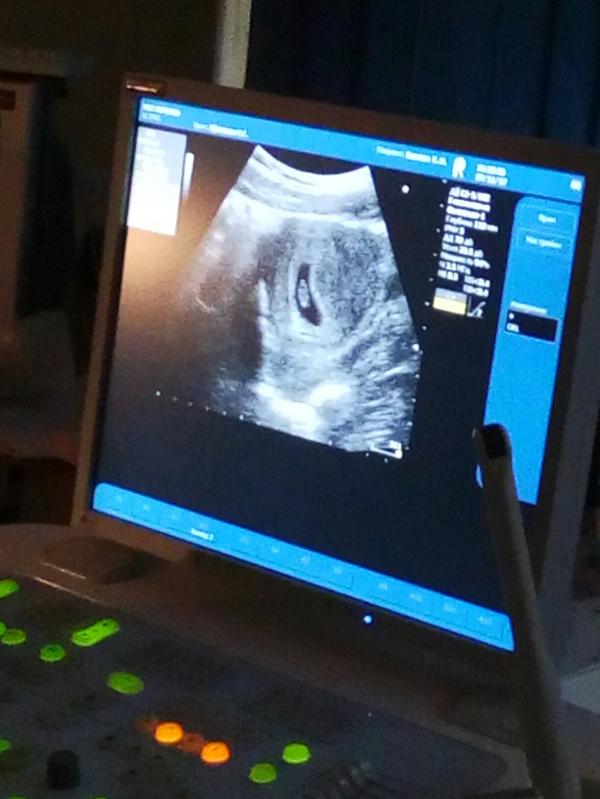

Боли не прекратились, поднялась температура. Поехала я в род дом. Меня посмотрели, сделали узи. Сказали, воспалительный процесс в матке. Прописали антибиотики... амосин 3 раза в день. Метронидозол 2 раза в день. Грудью кормить. Ребёнку давать Хилак форте 3 раза в день...

Повышенный тонус матки. Угроза была, угроза осталась. Я так почитала, мне вообще ничего делать нельзя. Физические нагрузки нельзя, эмоциональные нельзя (причем если это сильные эмоциональные нагрузки, то не важно негативные или позитивные - одинаково плохо). Невысыпаться нельзя. Сидеть в одной позе нельзя, в другой тоже. Да и вообще сидеть на одном месте более 30 минут нельзя. Встань, походи, разомнись, но делай это настолько плавно, чтобы не было никакой нагрузки...